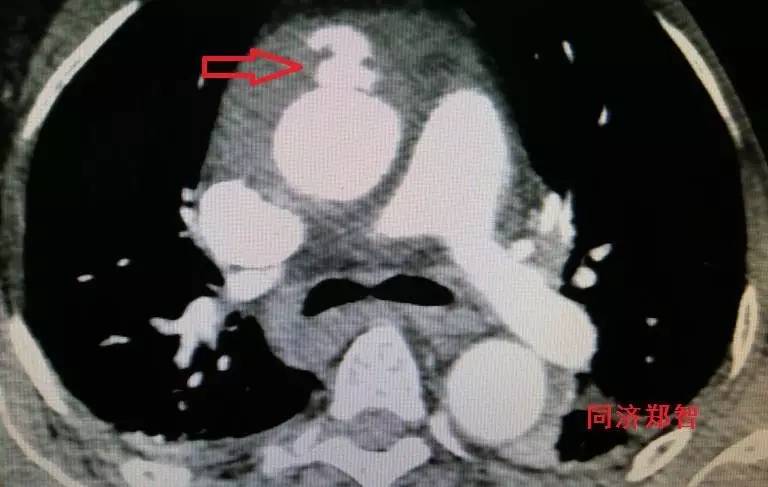

有时候平扫CT也能从血管内密度影的不同来诊断主动脉壁间血肿(图3)。平扫CT提示右肺动脉层面的升主动脉外侧为新月状稍亮的影(红箭头所示)。

图3

CT增强后证实为升主动脉壁间血肿(图4),如红箭头所示。

图4